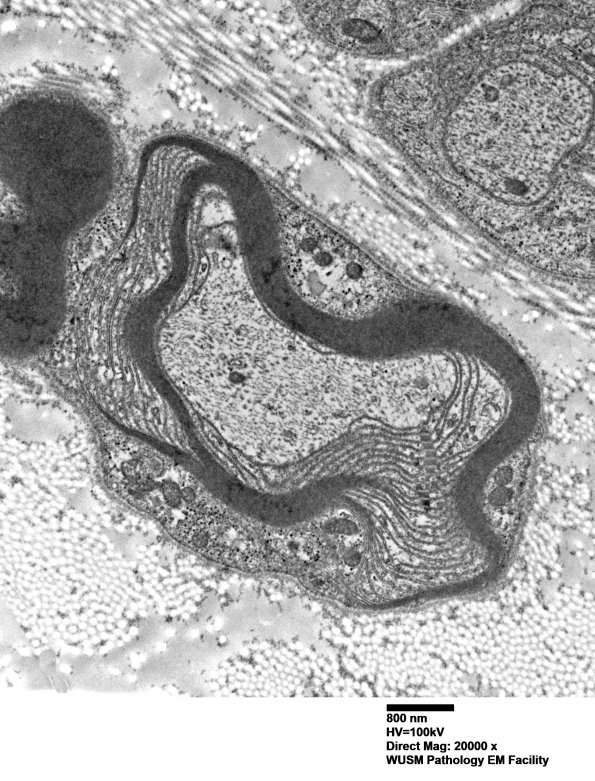

3A3A,B Much of the circumference is enveloped by UCM; however, the hemidesmosomes are unusual for UCM but may reflect a normal axonal substructure enveloped into the UCM. (electron micrographs)